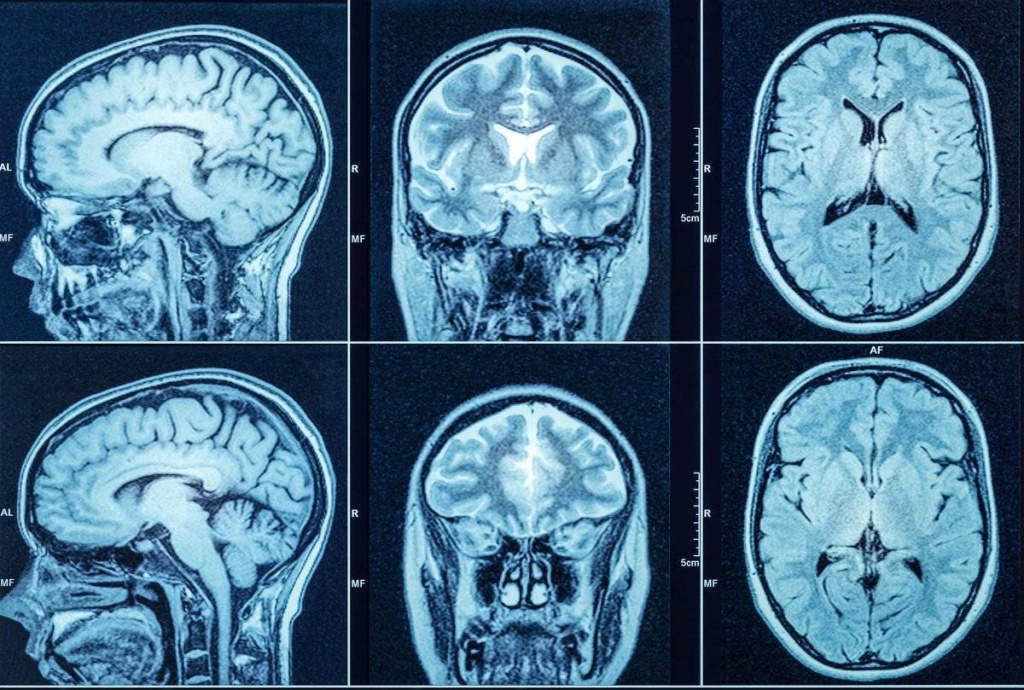

МРТ мозга – для определения степени поражения мягких тканей.